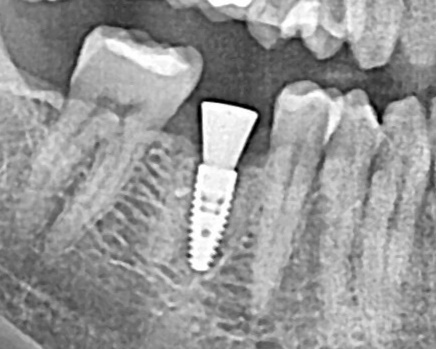

Очередной пример простой имплантации

в области зуба 46.

Сложность 1/10.

Время 20 мин.

Объёма костной ткани и объема слизистой более чем достаточно.

Условия идеальные.

Установлен имплант Inno implants 4,5x10mm.

Установлен формирователь.

Ещё один простой случай имплантации

в подготовленную кость.

Пациент обратился из другой клиники по рекомендации врача—ортопеда.

Врач высказал пожелания по модели импланта, 3D позиции импланта и дальнейшему протезированию.

В область зуба 25 был установлен имплант Astra tech.

Установлен формирователь слизистой.

Произведена пластика мягких тканей.

От временного протезирования пациент отказался.

Сложность операции 2/10.

Время работы 20 мин.

P.S. Стараюсь проводить максимальный объём возможных манипуляций за одну операцию.

Возможно это не соответсвует «классике» — но так работают все продвинутые хирурги в мире.

На практике уменьшение количества этапов приводит к лучшим результатам - сокращению времени проведённом пациентом в кресле и уменьшению сроков реабилитации пациента.

На фото показано операционное поле на момент операции и через 7 дней в момент снятия швов.